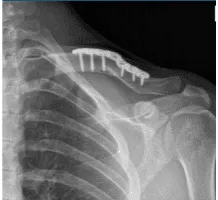

Se presentó una XR en la consulta y se encontró fractura clavicular en el centro del diástico con 1 cm de sobreposición y desplazamiento moderado. Las fracturas de la clavícula en la diáfise media son lesiones traumáticas frecuentes producidas por un impacto directo en la cintura escapular, y son más comunes en adultos jóvenes y activos.

Clavícula izquierda en posición AP

Finalmente, se colocó la placa y se realizó la compresión usando un tornillo de compresión. Se usaban dos tornillos no bloqueantes g y uno de bloqueo a cada lado. Se tomaron las imágenes finales y se consideraron satisfactorias. Se guardaron las imágenes finales.

El paciente fue extubado y trasladado a la unidad de recuperación postoperatoria en estado estable. Tras dos semanas, el paciente se registró, con XR presentada y sin lucidez periprotésica. La articulación esternoclavicular muestra alineación normal.

Resultados de la radiografía de 4 semanas de la clavícula izquierda tras la cirugía